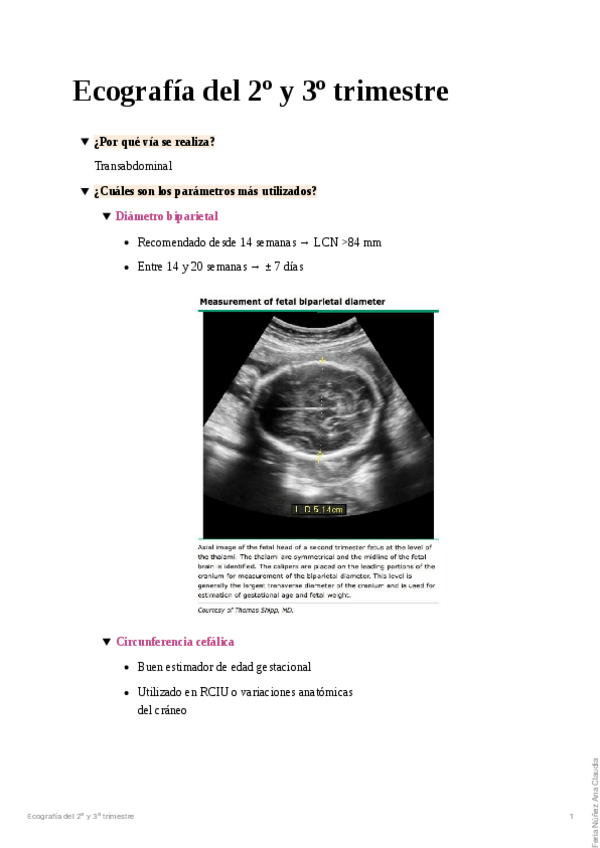

He publicado nuevos apuntes de 10º Habilidades en Ginecología y Obstetricia: Ecografia del I trimestre.pdf